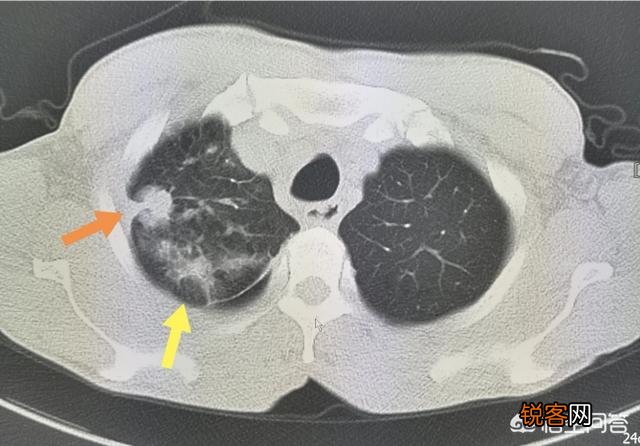

像上图这位男子 。才48岁 。间断胸疼半年多 。最近加重 。还出现咳嗽症状 。CT发现肺癌已经侵犯胸膜 。并且发生多发淋巴结转移 。已经没有手术治愈的机会了 。